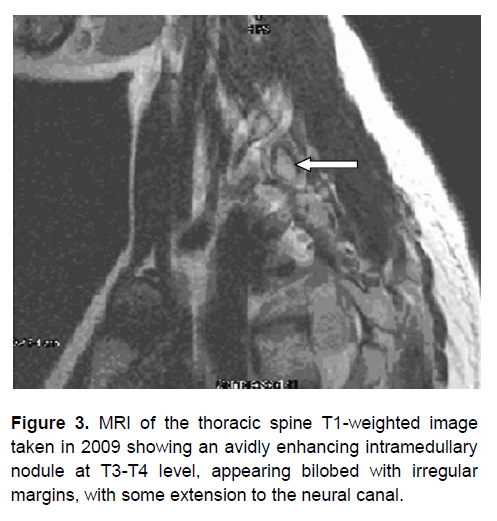

However, in March 2009, the patient developed gradual progressive weakness of both lower extremities, leading to paralysis. A repeat MRI of the thoracic spine showed an avidly enhancing intramedullary nodule at T3-T4 level, appearing bilobed with irregular margins, measuring 1.13 cm x 1.65 cm x 1.63 cm. The nodule was slightly hyperintense in T1-weighted study (Figure 3) and hypointense on T2-weighted imaging, with some extension to the neural canal at the level of T3-T4. A second laminectomy with tumor excision was done in May 2009. Histopathologic examination of the excised 2 cm x 1.5 cm x 0.5 cm mass revealed colloid material within the lumen of follicles or ducts (Figure 4) with papillary architecture and nuclear features consistent with papillary carcinoma. These findings were not seen in the histopathologic examination of the first surgical specimen. Microscopic sections from the second surgical specimen stained positively for thyroglobulin, thyroid transcription factor-1 (TTF-1) and epithelial membrane antigen (EMA) (Figures 5 to 7). The pathologic diagnosis of papillary carcinoma, suggestive of a thyroid primary, supersedes the previous histopathologic diagnosis. Thyroid ultrasound was normal. Thyroid function testing was also normal: thyroid stimulating hormone (TSH) was 1.03 µIU/mL (normal value 0.35 to 4.94), total thyroxine was 9 µg/dL (normal value 4.9 to 11.7), and total triiodothyronine was 1.24 ng/mL (normal value 0.58 to 1.59). Metastatic workup including CT scans of the neck, chest and abdomen did not reveal any metastatic foci.

Figure 3. MRI of the thoracic spine T1-weighted image taken in 2009 showing an avidly enhancing intramedullary nodule at T3-T4 level, appearing bilobed with irregular margins, with some extension to the neural canal.